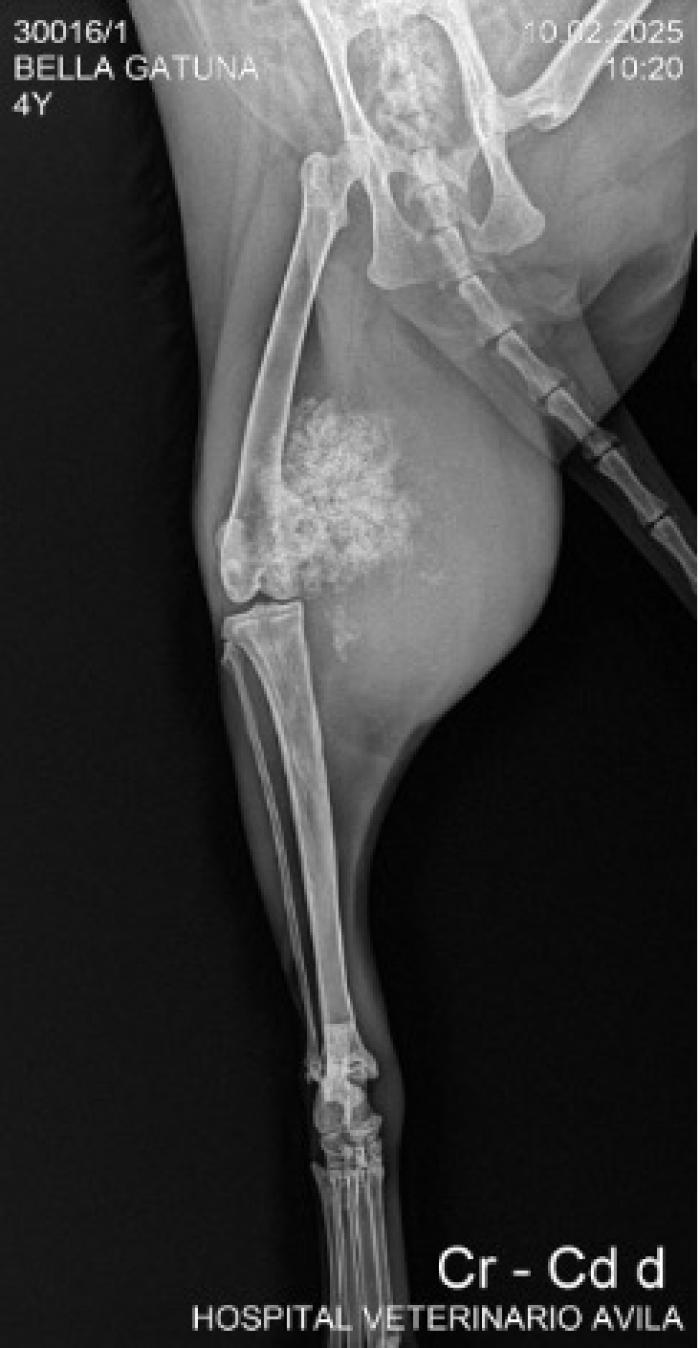

Radiografía

Se identificó una masa de densidad mineral heterogénea, con patrón mixto geográfico-agresivo, reacción perióstica desorganizada y mineralización en tejidos blandos adyacentes. Estos hallazgos son altamente sugestivos de una neoplasia ósea de origen condrogénico (Figura 1).